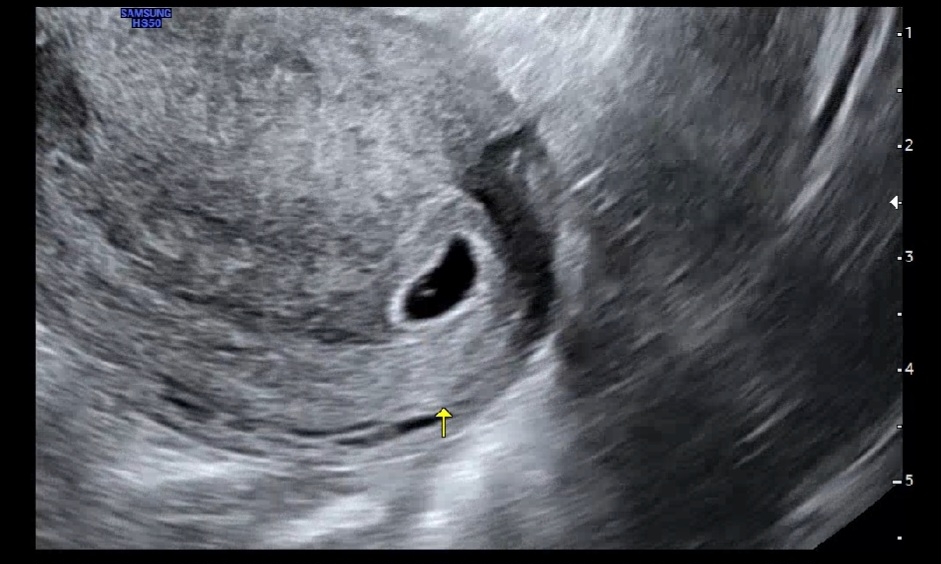

난황 보고 와써요 🥰

네이버 주수로는 6주 인데 생리주기가 달라서 5주인거 같아요 다음주에 심소 들으러 가요 ㅎㅎㅎㅎ 아직 콩알만해서 아직도 임신이 얼떨떨해요